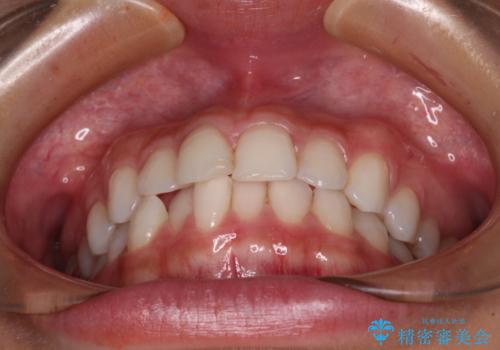

- 歯並びと虫歯をきれいにしたいとのことで来院された患者様です。

楽して短期間で歯列を整えたいとのことで、ワイヤー装置を用いて矯正治療を行い、矯正治療後に下顎の虫歯はセラミックインレー、上顎はPGAインレー(ゴールドインレー)、根管治療を行う歯についてはオールセラミッククラウンにて補綴治療を行うこととしました。

矯正治療は8ヶ月ほどで終了し、速やかに虫歯治療に移行することができました。

保険治療で用いる樹脂(コンポジットレジン)で行った虫歯治療は、周辺が変色して汚くなっていましたが、下顎はセラミックインレーで審美的に、上顎はPGAインレーで歯に負担の少ない治療を行うことができました。